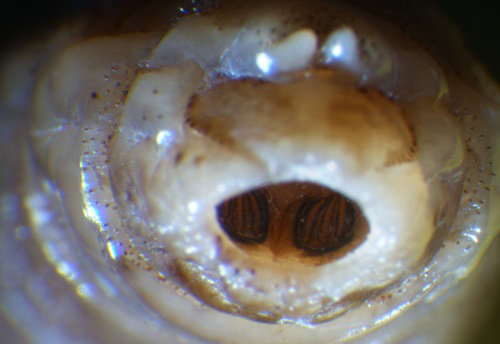

• L3 à plaques stigmatiques enfoncées dans le dernier segment, avec 3 fentes stigmatiques rectilignes convergeant vers le bouton